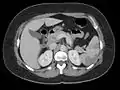

| Blood clots in the ventricle found on autopsy |

Echocardiography is the main diagnostic tool for LVT. A distinct mass is visible in the left ventricle. Computed Tomography and Magnetic Resonance Imaging are effective, but less common ways to detect LVT, due to their costs and risks.[1] It is possible to assess whether a thrombus will become an embolus through echocardiography. Mobility and protrusion of the thrombus are two characteristics associated with increased embolic potential.[8]